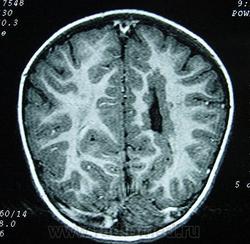

Гетеротопии. Перивентрикулярная гетеротопия. Субэпендимальная нодулярная (узелковая) гетеротопия.

Наиболее частым вариантом миграционных нарушений является гетеротопия - скопление нейронов, остановившихся в различных аномальных местах на пути следования к коре головного мозга. Такая остановка происходит не позже 5-го месяца внутриутробного развития. Изолированный участок узловатой массы называется «гетеротопион». В настоящее время описаны следующие варианты гетеротопии:

Перивентрикулярная субэпендимальная гетеротопия